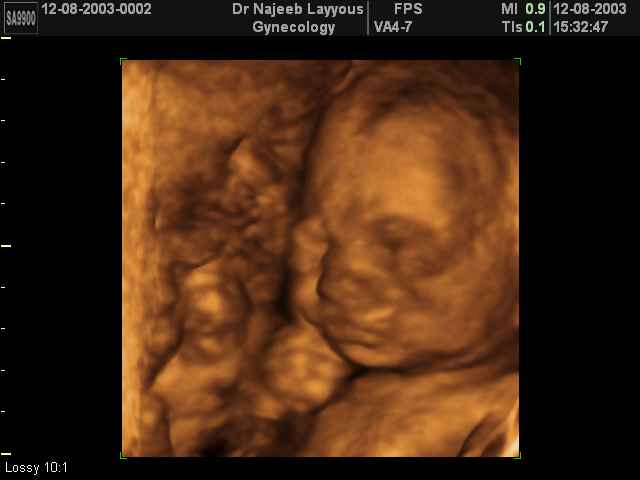

- Fetal Behavior Ultrasound Photos

Ultrasound Photos in 3D showing Fetal Behavior Inside the uterus | Dr N Layyous